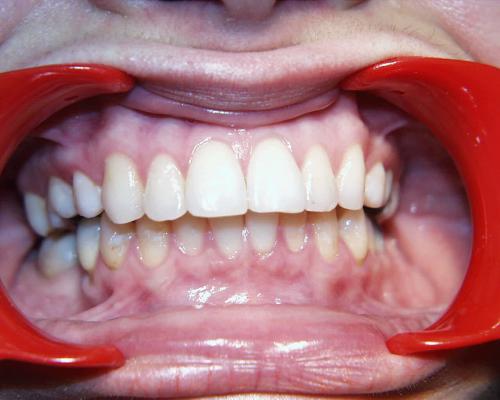

Links Zustand beim Einsetzen der festen Zahnspange, rechts Situation unmittelbar nach der Operation (nach 2 Jahren, 4 Monaten). Der Unterkiefer wurde chirurgisch vorgesetzt und dadurch die Zahnreihen besser in Kontakt gebracht. Die Operation wurde an der Uniklinik Homburg durchgeführt. Eine Feineinstellung der Verzahnung ist aber im Laufe der kieferorthopädischen Nachbehandlung noch erforderlich.